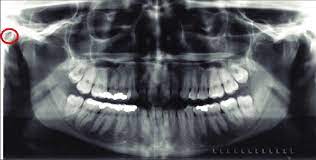

On examination, no wound was found in the neck and the external auditory meatus was packed, with no active bleed. 18 auricle and external acoustic meatus noritaka komune, junichi fukushima, and albert l. The auricle is susceptible to environmental influences and trauma. The external auditory meatus a.k.a. What muscle will the parotid gland duct/stensen's duct penetrate? The medial 1/3 of the external acoustic meatus is bony and the lateral 2/3 is formed by cartilage: It lies obliquely at the medial end of external auditory meatus forming major part of lateral wall of middle ear cavity. It can be divided based either on its structural composition or its shape. It is also cosmetically important and its anatomical structures are… So in order to check the tympanic membrane the pinna requires to be pulled upwards. It consists of a bony (inner) portion and a fibrocartilaginous (outer) portion, the cartilaginous external acoustic meatus. What are the characteristics of the parotid gland? External acoustic meatus extends from the base of the concha towards the tympanic membrane and alongside its posterior wall measures nearly 24 millimeters.

Quizlet is the easiest way to study, practice and master what you're learning. The medial 1/3 of the external acoustic meatus is bony and the lateral 2/3 is formed by cartilage: How to say external acoustic meatus in english? Meatus acusticus externus ta, acoustic meatus (1) ,. In case of a ceruminal obstruction, an adequate assessment of the external auditory meatus should be done only after cleaning, which may demask existing dermatosis. The external acoustic meatus (auditory canal) is a narrow chamber situated in the _____ bone. An example is the external acoustic meatus, also known as the ear canal, which connects the middle and outer ear. It consists of a bony (inner) portion and a fibrocartilaginous (outer) portion, the cartilaginous external acoustic meatus. External acoustic meatus extends from the base of the concha towards the tympanic membrane and alongside its posterior wall measures nearly 24 millimeters. A, osseous external acoustic meatus covered by tympanic membrane. The cerumen may mask existing diseases of the skin in the entrance of the external ear canal. On examination, no wound was found in the neck and the external auditory meatus was packed, with no active bleed. It is also cosmetically important and its anatomical structures are…